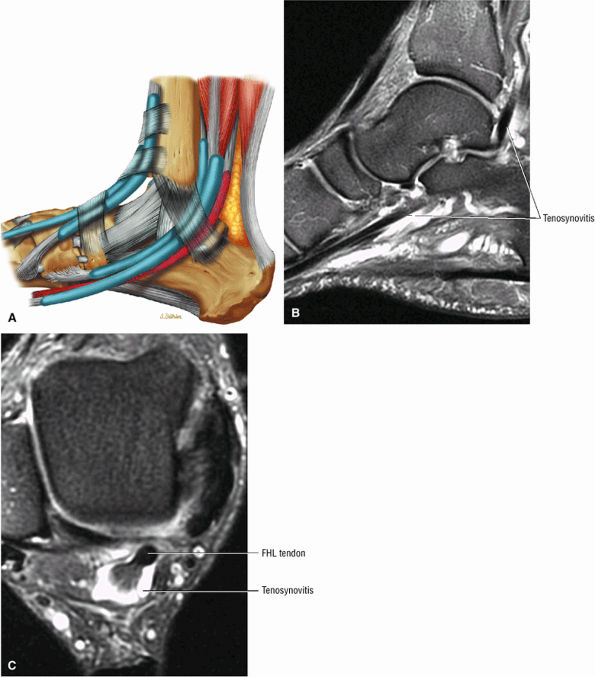

FIGURE 5.9 ● FLEXOR HALLUCIS LONGUS The flexor hallucis longus (FHL) flexes the great toe and plantarflexes the foot. The FHL is susceptible to injury during extremes of ankle plantarflexion and metatarsophalangeal dorsiflexion. The proximal sheath, 10 to 12 cm in length, has no mesotenon and may communicate with both the ankle joint and the sheaths of the flexor digitorum longus and tibialis posterior.

|